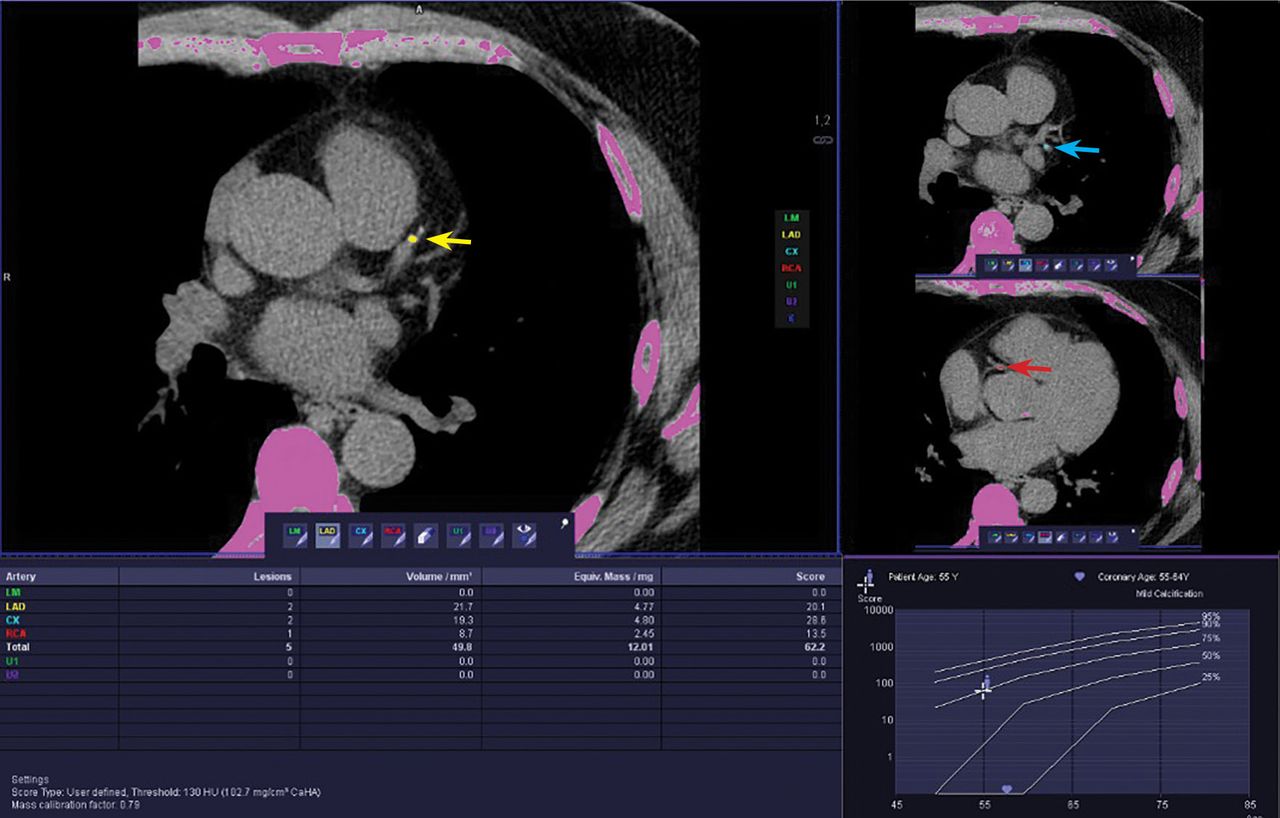

Coronary Artery Calcium Scoring. Examples Of Coronary Artery Calcium

www.researchgate.net

www.researchgate.net

Frontiers | Prognostic Value Of Coronary Artery Calcium Score In

www.frontiersin.org

www.frontiersin.org

score coronary artery calcium lad cac mild frontiersin prognostic hospitalized descending moderate anterior zero fcvm